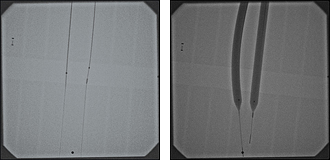

All EZDilate Balloon Dilators have a fully radiopaque tip as well as two radiopaque marker bands within the balloons to signify the distal and proximal ends of maximum dilation.

These navigation aids provide assurance of precise visualization that the device is in the desired location prior to inflation.

Radiopaque Tips